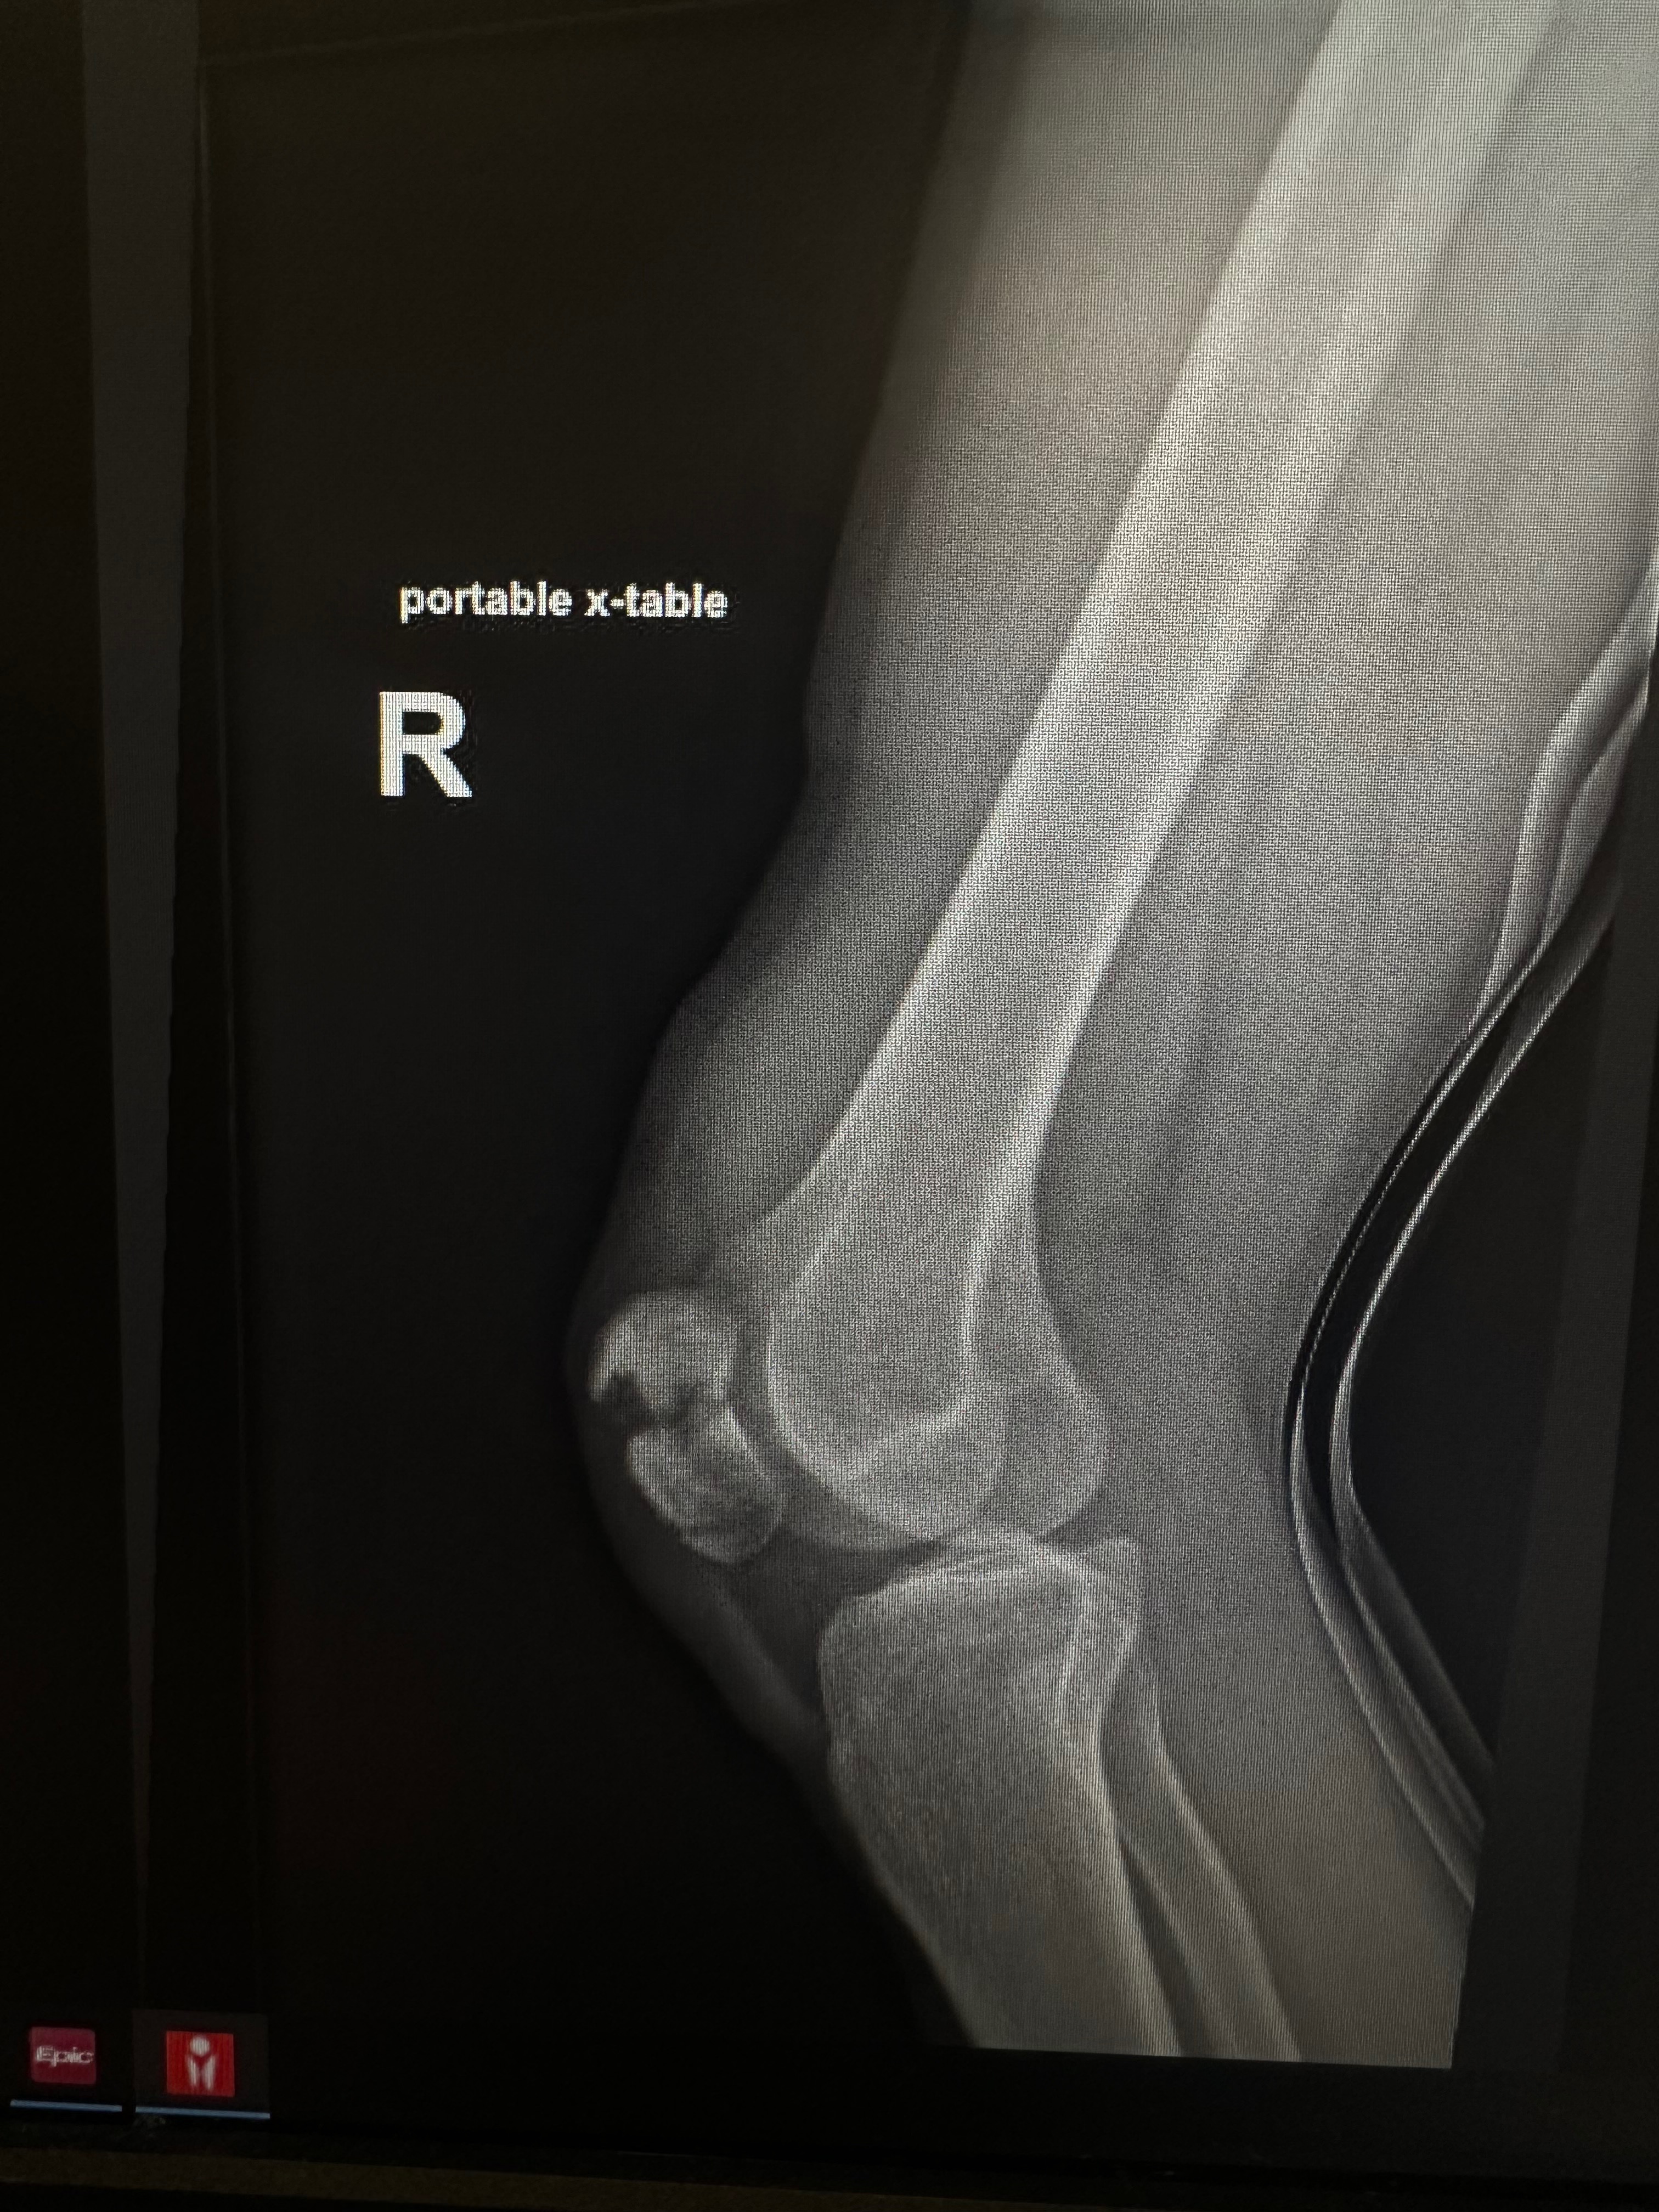

Charlie fractured their kneecap in two places. Charlie spent an intense night in the ER and has since then gone through surgery to help the knee heal properly. Charlie will be in a solid cast for many weeks and then will need to undergo many rounds of PT before they can return to work or get riding on a bike again.